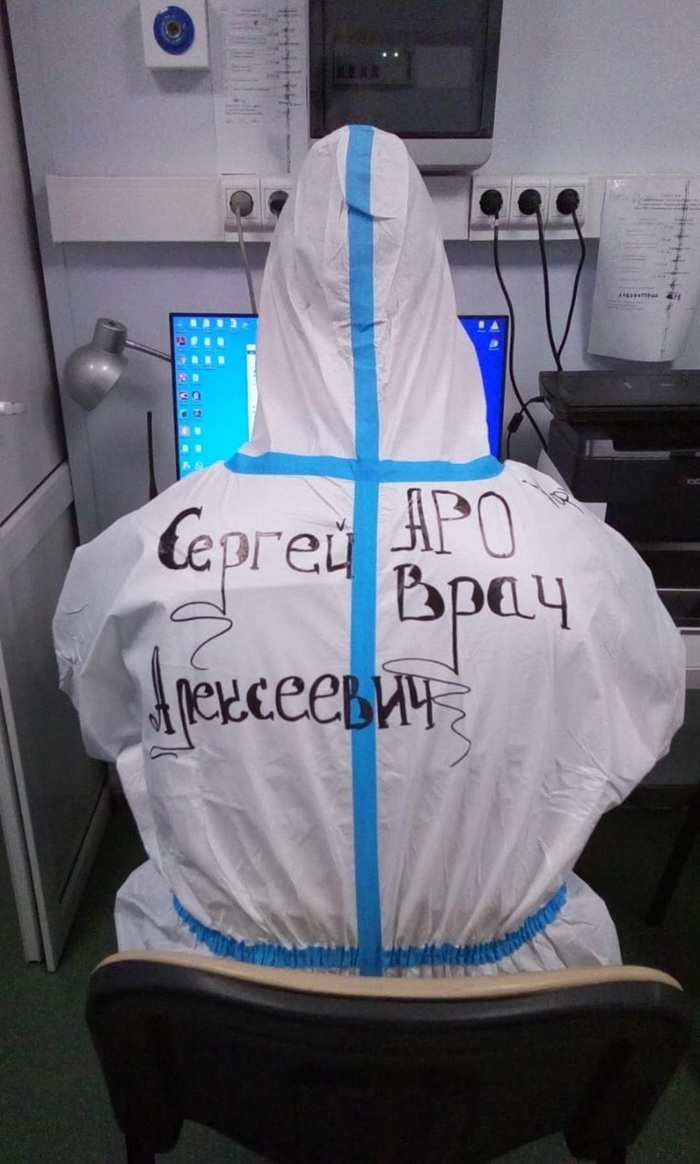

-Палыч, можешь не искать, дай центр.

- Танечка, радость моя, значит смотри, я тебя сейчас в шею уколю и поедем в больницу.

Через водительскую дверь, задние заблокированы, залезаю назад, Палыч даёт катетер и светит фонарем, чуть откидываю Татьяну и мою шею. Пожалуй самая экзотичная постановка внутренней Яремы ( внутренней яремной вены). Самый ближний доступ, из всех доступных самый близкий к верхушке легкого, более подходящий для пункции, но из дальнего в условиях гоповолемии и сидячего положения я ее просто не поймаю и это точно не подклюк.

Значит аллергии на новокаин нет, погнали. Как же все таки не удобно: ножки sternocleidomastoideus, удар 45 градусов, направление на сосок 1,5-3 см. Одышка не делает лучше, но иначе она не может. Отлично. Контроль крови в шприце.

-Палыч, струна.

Кто хоть раз работал с российскими центрами меня поймёт, там от струны, одно название, волосок.

- Держи.

Струна вошла, игла выходит, расширитель для катетера.

-Танечка, потерпи,- с этими словами, вкручивающими движениями захожу, вытаскиваю,-Палыч катетер.

-Ага.

Отлично 8-10 см, что бы не упасть в правый желудочек.

-Палыч литр физа, давай полечим девочку, с ее резко отрицательным ЦВД (центральным венозным давлением) и давай фиксанемся.